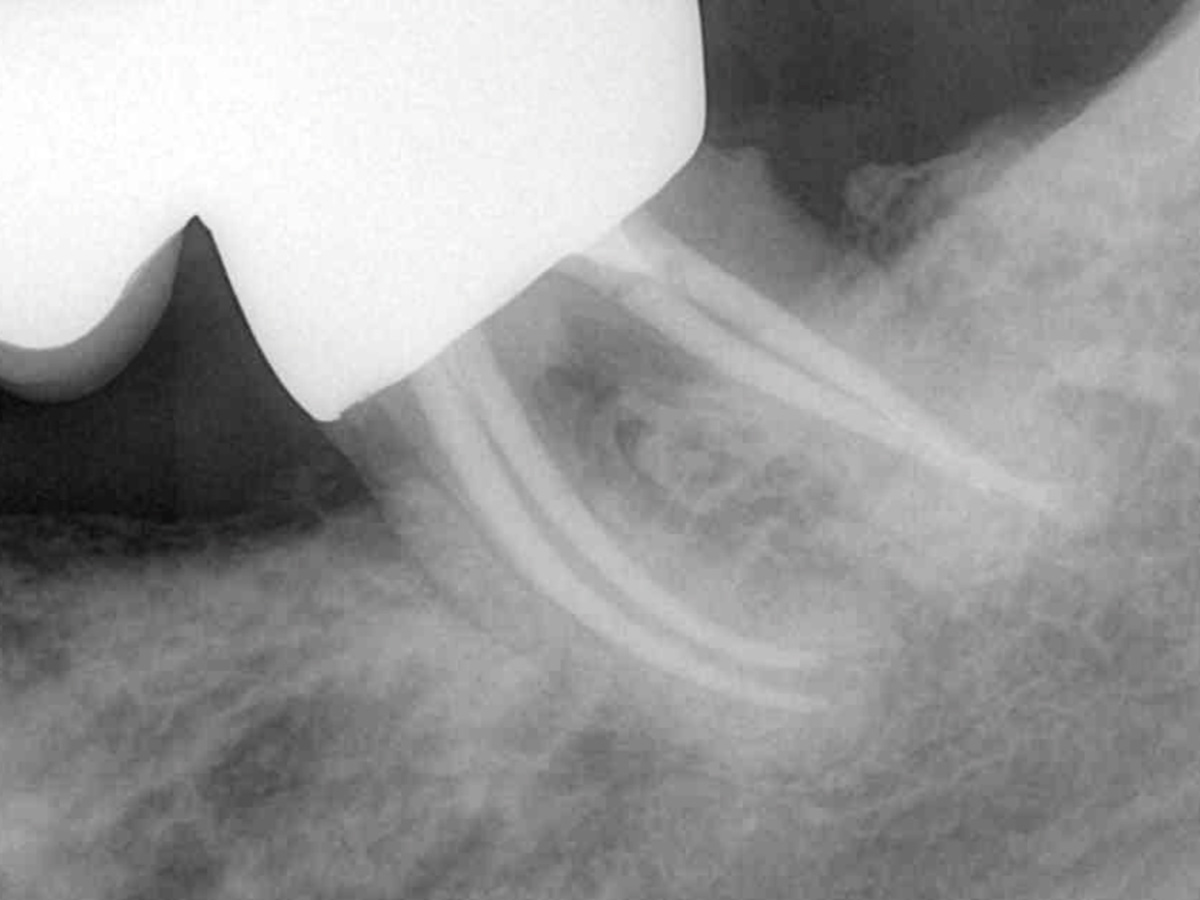

• Warm-VertikaleKondensation

• Kalt-Hydraulische Kondensation

• Vorhersagbare Wurzelfüllung bei unterschiedlichen Kanalkonfigurationen

• Effektive Entfernung von Guttapercha